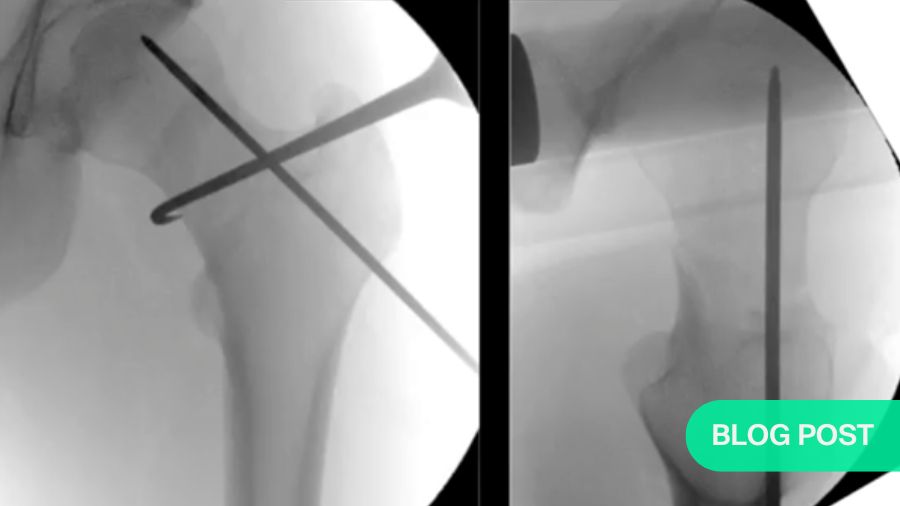

Sommer’s preferred strategy is to apply traction to the affected leg, then turn it inward until the two parts of the femoral neck line up. With the bones roughly aligned, he then uses minimally invasive techniques to remove any bone fragments. Then, relying on vertical and horizontal fluoroscopic views, he can fine-tune the alignment before completing the fixation. One innovative trick he uses is to insert a hook into the fracture site to pull the separated ends into position. He then uses a Femoral Neck System (FNS) implant to fix the fracture.

The FNS (shown below) has only four parts: a plate, a bolt, an anti-rotation screw and a locking head screw. K-wires can be used to hold the bone fragments temporarily in place. The result is highly-reliable fixation (<.2% failure rate based on 30000 implantations) that requires a minimal incision, leaving a small surgical footprint with no protruding parts, centric positioning of the neck screw or bolt and solid resistance against rotation. Additionally, it is compact enough for use in Asian patients, who often have rather small femoral necks.